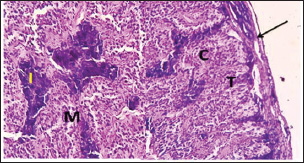

Fig. 2. photomicrograph section in adrenal of swan geese illustrated: the capsule (black arrow) sent trabeculae (T), cortical cords (C), medullary tissue (M), and islets of chromaffin cells (I). (H&E Stain) 100X)

The adrenal glands of swan geese are covered with thin capsules of connective tissue rich in blood capillaries. Thin and short trabecular ions were sent from the capsule to the interior of the gland (Fig. 2). There were two intermingled types of tissue constituting the gland parenchyma: the medullary and cortical tissues (Figs. 3 and 4). The capsule in females is thicker than in males (Table 2). During the histological examination, no boundaries between the cortex and medulla were observed.

The adrenal glands were subdivided into the central zone, the peripheral zone, and the subcapsular layer. The main composition of the central and peripheral zones was cortical cells, whereas the subcapsular layer mostly contained medullary cells. Within the examinations, columnar acidophilic cells in the cortex portions were organized as cords that were cylindrically shaped and irregularly orientated. The cords of the central zone were smaller than those found in the peripheral zone and were mostly curved and straight in arrangement. The cells of cortical cords were small but more proportion to chromaffin medullary cells.

The medullary portion of the adrenal gland in swan geese is represented by small islets of chromaffin cells that are distributed irregularly between the cords of the cortex. The chromaffin cells were large, basophilic, and polygonal. The current investigation showed that the cortical tissue was in greater proportion in the adrenal of swan geese than the medullary tissues. The blood sinusoid was scattered within the gland between the cortical or medullary tissues, but those located in the peripheral zone were narrower than those located in the central zone (Fig. 5).